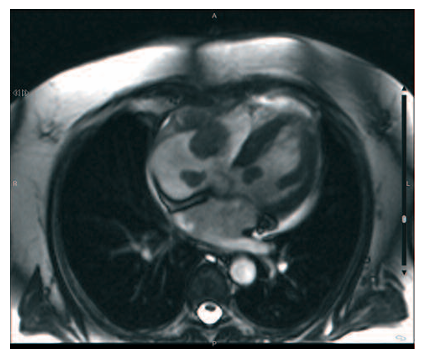

Plasmocitoma cardíaco secundario